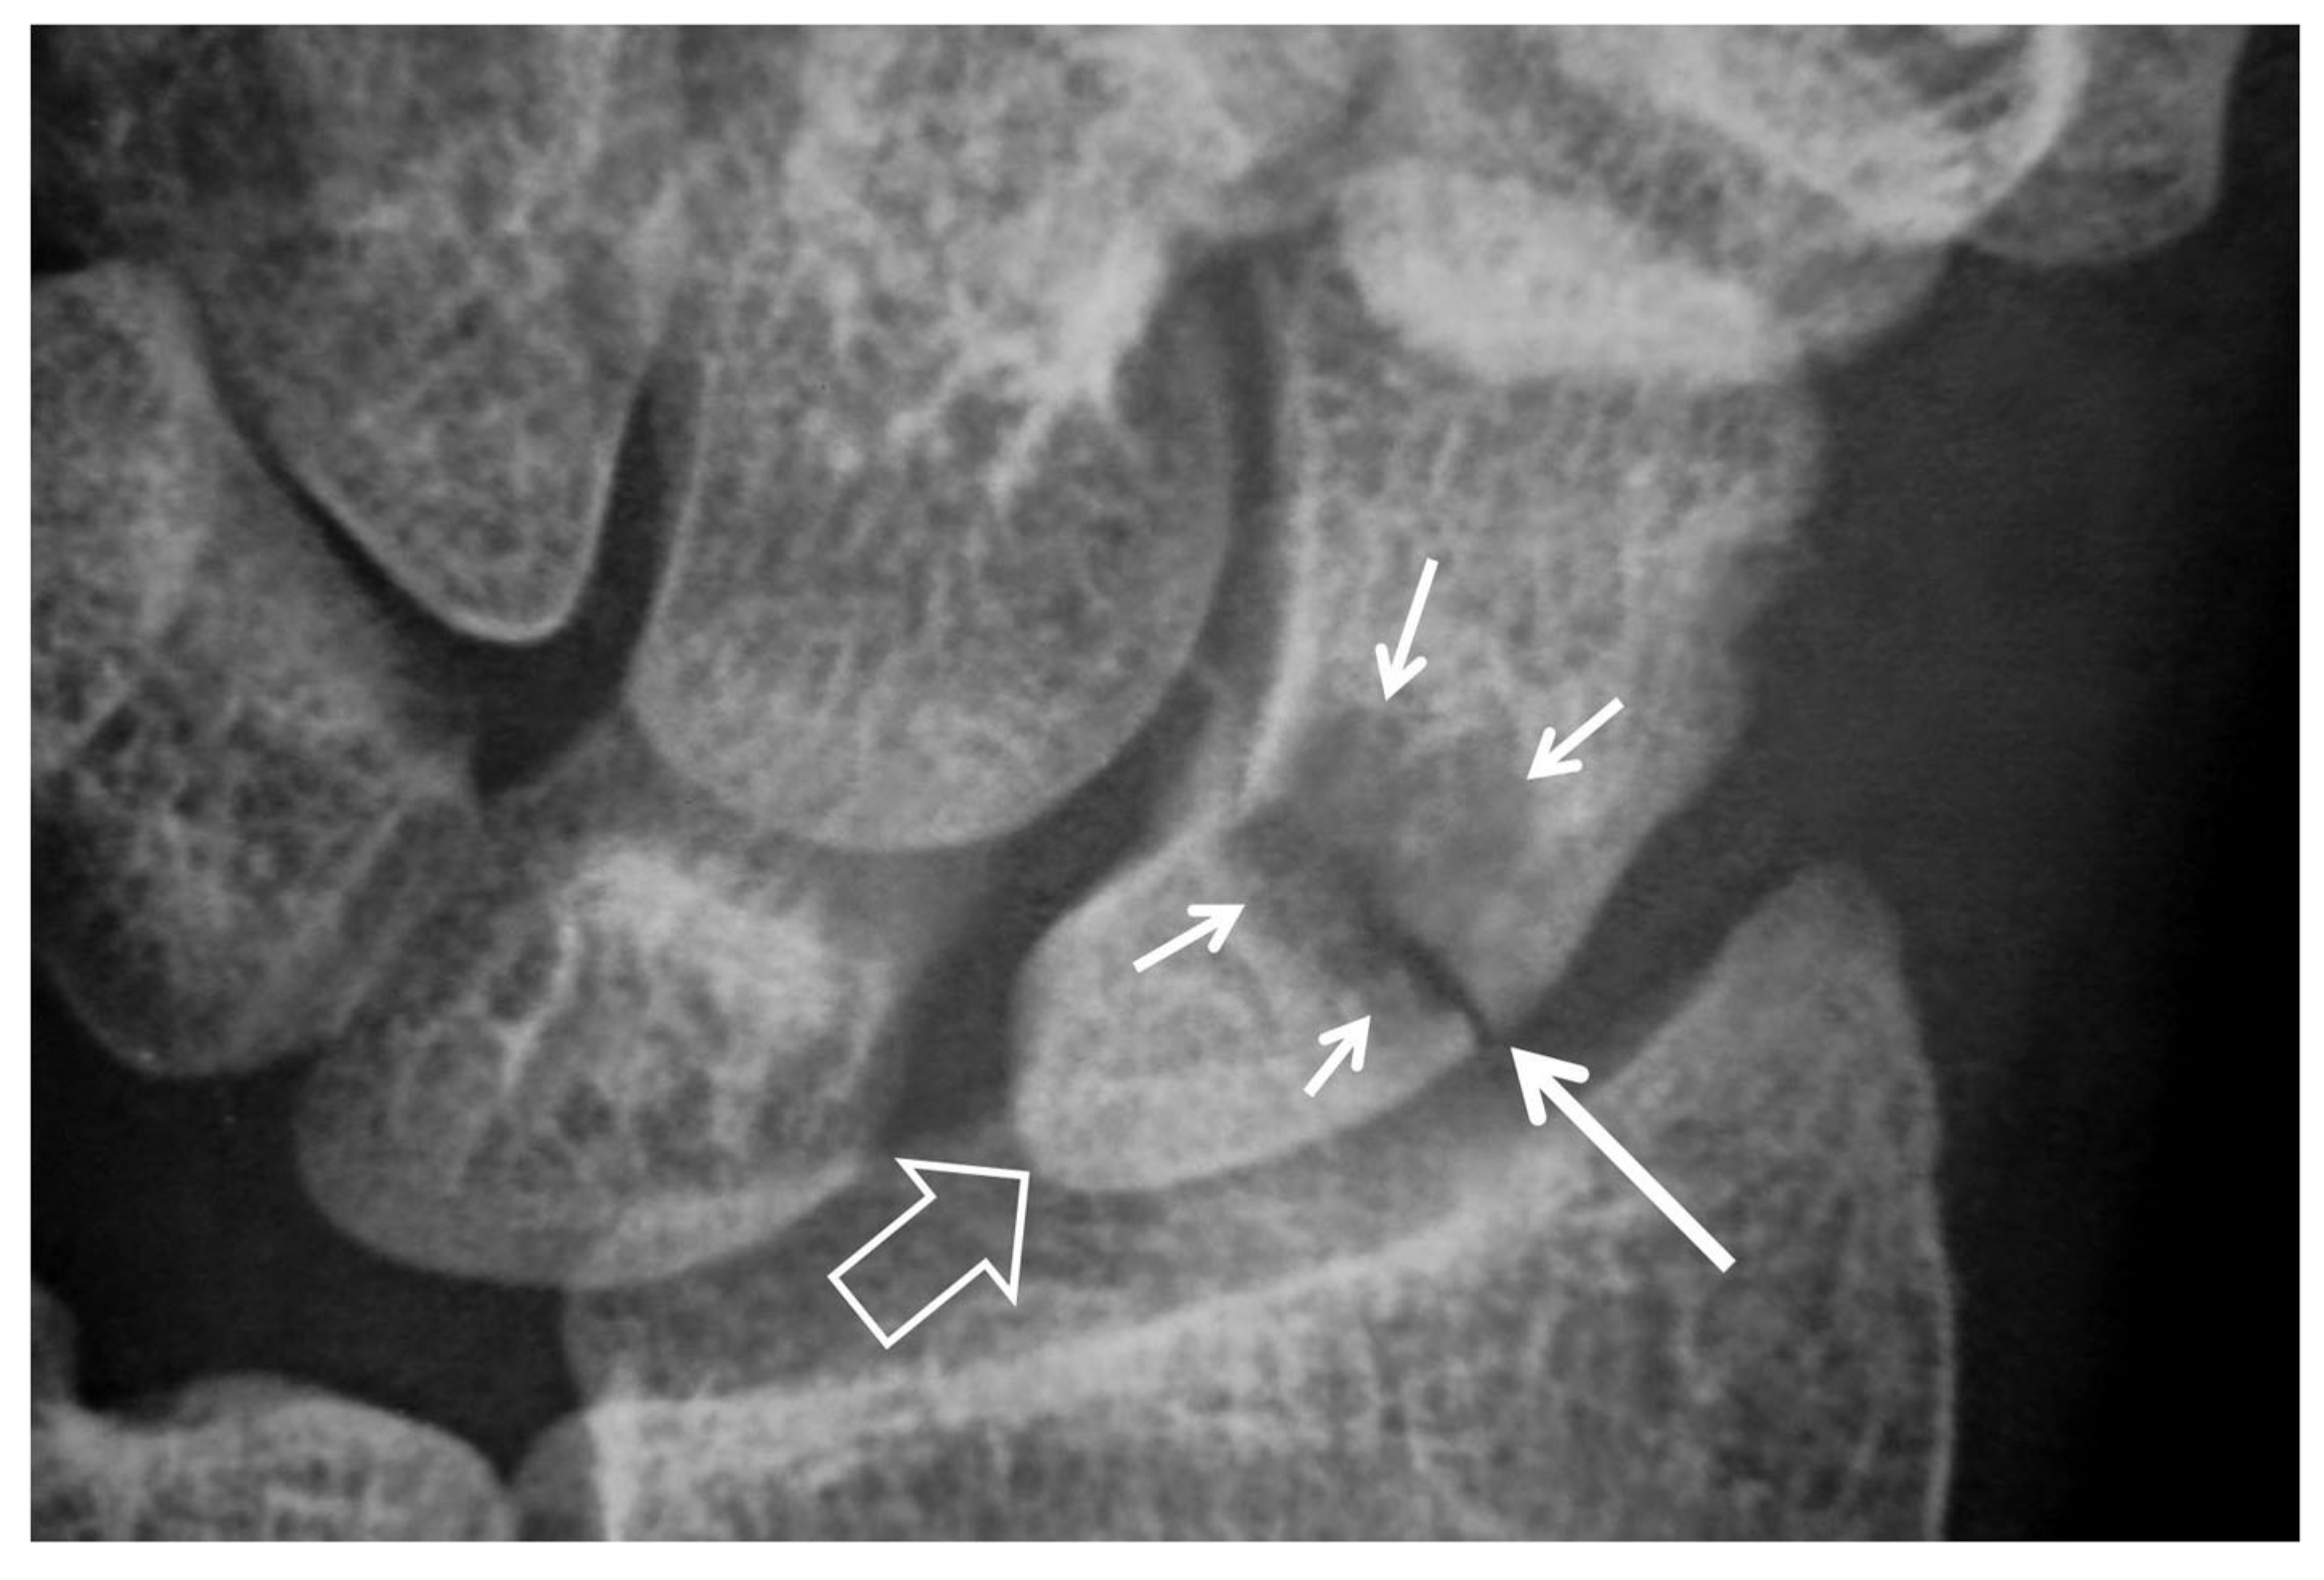

Figure 4.

A 55-year-old male patient with long standing wrist pain and limited range of motion. Scapholunate ligament disruption (large open arrow), radiolunate joint space narrowing (small open arrow) and mid-carpal osteoarthritis (arrows) are diagnostic of a SLAC wrist. The altered shape of the scaphoid is due to its rotatory subluxation.